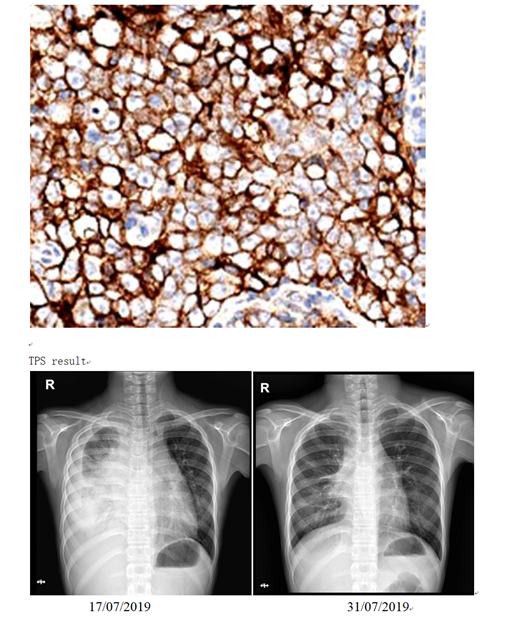

Case Description: Case 1, a 12-year-old female who was admitted for cough and serious neck swelling. PET-CT showed multiple lymph nodes enlargement in the whole body ;among them, the anterior mediastinal lesions were fused with each other and the boundary between adjacent large vessels was unclear; multiple lung and pleural metastasis . EB virus in blood was 7.48×104copies/mL.Bone marrow morphology: Naive lymphocytes account for 2.5%, some lymphocytes are irregular; Mature plasma cells easy to see.Bone marrow immunotypes: 0.56% CD19-CD5-CD10-abnormally mature B lymphocytes. Biopsy: (left neck lump) LELC, EBERs(+).Partial remission was achieved after 2 courses of paclitaxel / carboplatin/ apatinib protocal. Due to delay with varicella, the tumor came back. After the third course of treatment,she showed chest tightness and pleural effusion, EB virus in blood increased, PDL1 protein was TPS 80% positive. After one PD1 antibody combined with chemotherapy,lymph nodes and thoracic lesions significantly reduced (Image1-3), blood EB virus turned to negative. She is now continuing with PD1 inhibitor.